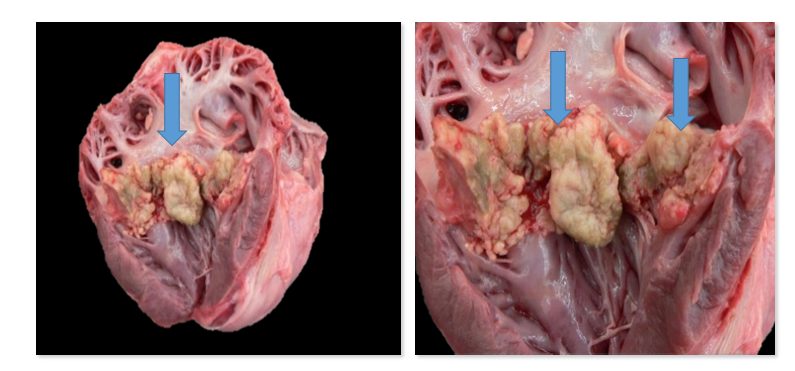

What is this?

Endocardiosis

What is endocardiosis and what are some characteristics?

NOT inflammatory!

Degenerative condition of the valve;

Small tiny bumps on free edge of valve leaflets, idiopathic, common in middle aged to older dogs, more common in AV valves (esp. bicuspid) than semilunar, can lead to eccentric hypertrophy, jet lesions may occur